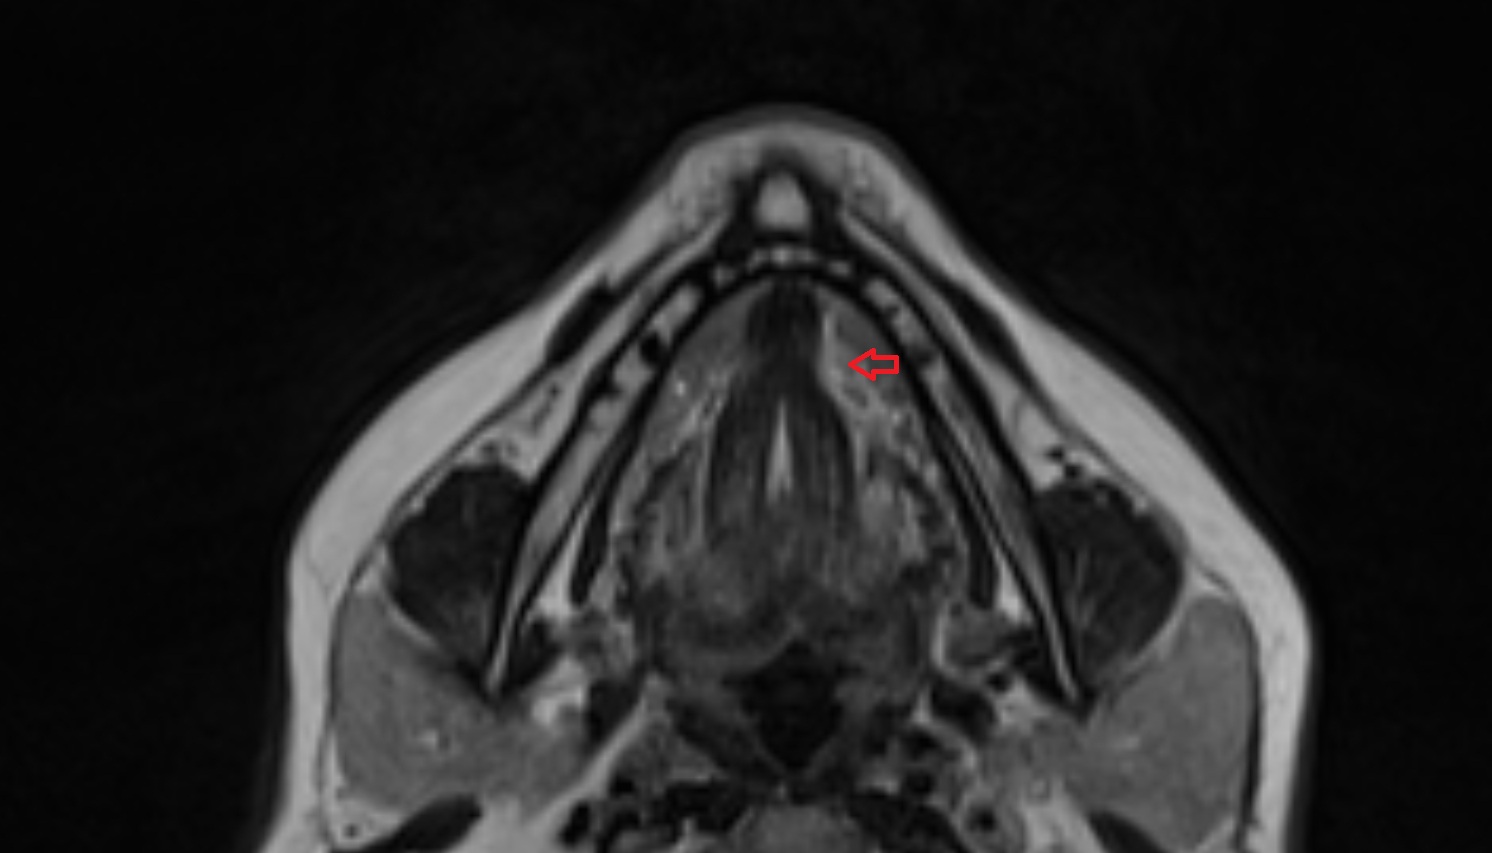

- Body of tongue

- Dorsum of tongue